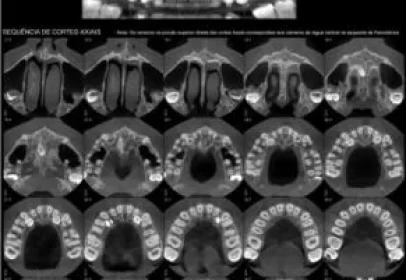

A tomografia da maxila, também conhecida como tomografia computadorizada da arcada dentária superior, é um exame de imagem que utiliza raios X e um computador para criar imagens detalhadas e...